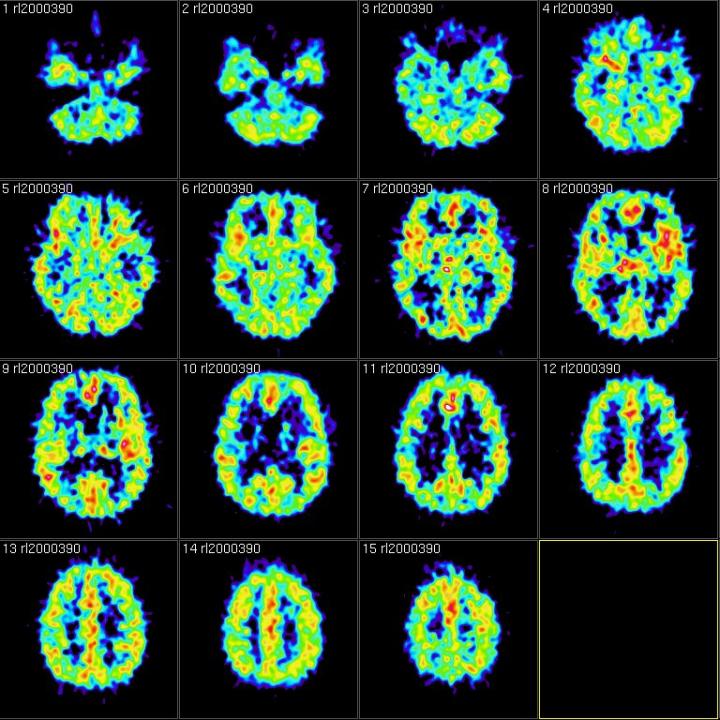

Since Ancient Greece, memory theorists have known that we use context -- or the situation we're in, including sights, sounds, smells, where we are, who we are with -- to organize and retrieve our memories. But the Dartmouth- and Princeton-led team wanted to know whether and how people can intentionally forget past experiences. They designed a functional magnetic resonance imaging (fMRI) experiment to specifically track thoughts related to memories' contexts, and put a new twist on a centuries-old psychological research technique of having subjects memorize and recall a list of unrelated words. In the new study, researchers showed participants images of outdoor scenes, such as forests, mountains and beaches, as they studied two lists of random words, manipulating whether they were told to forget or remember the first list prior to studying the second list.

"Our hope was the scene images would bias the background, or contextual, thoughts that people had as they studied the words to include scene-related thoughts," says lead author Jeremy Manning , an assistant professor of psychological and brain sciences at Dartmouth. "We used fMRI to track how much people were thinking of scene-related things at each moment during our experiment. That allowed us to track, on a moment-by-moment basis, how those scene or context representations faded in and out of people's thoughts over time."

The study's participants were told to either forget or remember the random words presented to them interspersed between scene images. Right after they were told to forget, the fMRI showed that they "flushed out" the scene-related activity from their brains.

But when the researchers told participants to remember the studied list rather than forget it, this flushing out of scene-related thoughts didn't occur. Further, the amount that people flushed out scene-related thoughts predicted how many of the studied words they would later remember, which shows the process is effective at facilitating forgetting.

The second implication is more subtle but also important. "It's very difficult to specifically identify the neural representations of contextual information," Manning says. "If you consider the context you experience something in, we're really referring to the enormously complex, seemingly random thoughts you had during that experience. Those thoughts are presumably idiosyncratic to you as an individual, and they're also potentially unique to that specific moment. So, tracking the neural representations of these things is extremely challenging because we only ever have one measurement of a particular context. Therefore, you can't directly train a computer to recognize what context 'looks like' in the brain because context is a continually moving and evolving target. In our study, we sidestepped this issue using a novel experimental manipulation -- we biased people to incorporate those scene images into the thoughts they had when they studied new words. Since those scenes were common across people and over time, we were able to use fMRI to track the associated mental representations from moment to moment."